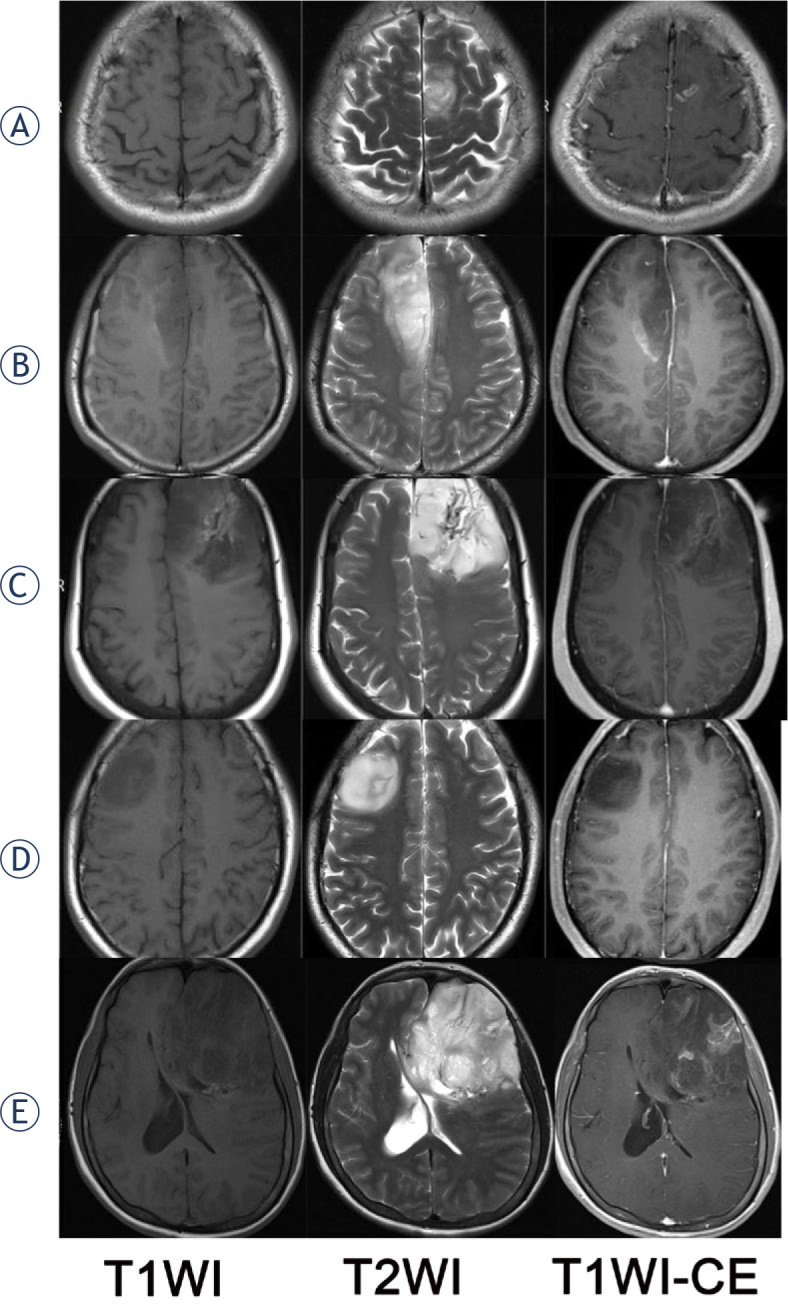

研究背景该研究旨在探讨影像学坏死(Imnecrosis)在胶质瘤分级中的诊断价值,预测胶质瘤的基因型和预后,并通过动态对比增强磁共振灌注成像(DCE-MRI)进一步评估肿瘤坏死:我们回顾性地纳入了150例经病理证实为成人弥漫性胶质瘤的患者(104例男性,平均年龄46岁),所有诊断均基于2021年世界卫生组织(WHO)中枢神经系统(CNS)分类。收集了病理坏死(Panecrosis)和基因突变信息。所有患者均接受了常规和 DCE-MRI 检查,并一直随访至 2021 年 5 月 31 日。Imnecrosis由两名经验丰富的神经放射科医生确定。DCE-MRI得出的指标图经过后处理,记录了肿瘤实质、瘤周和对侧区域每个指标的平均值:在定义瘤体坏死时,观察者之间的一致性很高(Kappa = 0.668,p < 0.001),瘤体坏死和泛坏死之间的一致性也很高(Kappa = 0.767,p < 0.001)。与低级别胶质瘤相比,高级别胶质瘤有更多的Imnecrosis(85.37%,P<0.001),并且Imnecrosis随着胶质瘤级别的增加而显著增加。IDH-野生型、1p19q-非缺码和CDKN2A/B-杂合子缺失胶质瘤中的Imnecrosis明显增多。通过多变量考克斯回归分析,脑坏死是胶质瘤的一个独立且不利的预后因素(危险比=2.113,p=0.046)。此外,DCE-MRI得出的肿瘤实质中血管外细胞外体积分数(ve)在鉴别Panecrosis和Imnecrosis方面显示出最高的诊断效率,特异性很高(分别为83.3%和91.9%):结论:Imnecrosis可为胶质瘤的分级、基因型和预后预测提供Panecrosis之外的补充证据,而肿瘤实质中的ve可帮助预测肿瘤坏死,且特异性高。

Background: The aim of the study was to investigate the diagnostic value of imaging necrosis (Imnecrosis) in grading, predict the genotype and prognosis of gliomas, and further assess tumor necrosis by dynamic contrast-enhanced MR perfusion imaging (DCE-MRI).

Patients and methods: We retrospectively included 150 patients (104 males, mean age: 46 years old) pathologically proved as adult diffuse gliomas and all diagnosis was based on the 2021 WHO central nervous system (CNS) classification. The pathological necrosis (Panecrosis) and gene mutation information were collected. All patients underwent conventional and DCE-MRI examinations and had been followed until May 31, 2021. The Imnecrosis was determined by two experienced neuroradiologists. DCE-MRI derived metric maps have been post-processed, and the mean value of each metric in the tumor parenchyma, peritumoral and contralateral area were recorded.

Results: There was a strong degree of inter-observer agreement in defining Imnecrosis (Kappa = 0.668, p < 0.001) and a strong degree of agreement between Imnecrosis and Panecrosis (Kappa = 0.767, p < 0.001). Compared to low-grade gliomas, high-grade gliomas had more Imnecrosis (85.37%, p < 0.001), and Imnecrosis significantly increased with the grade of gliomas increasing. And Imnecrosis was significantly more identified in IDH-wildtype, 1p19q-non-codeletion, and CDKN2A/B-homozygous-deletion gliomas. Using multivariate Cox regression analysis, Imnecrosis was an independent and unfavorable prognosis factor (Hazard Ratio = 2.113, p = 0.046) in gliomas. Additionally, extravascular extracellular volume fraction (ve) in tumor parenchyma derived from DCE-MRI demonstrated the highest diagnostic efficiency in identifying Panecrosis and Imnecrosis with high specificity (83.3% and 91.9%, respectively).

Conclusions: Imnecrosis can provide supplementary evidence beyond Panecrosis in grading, predicting the genotype and prognosis of gliomas, and ve in tumor parenchyma can help to predict tumor necrosis with high specificity.